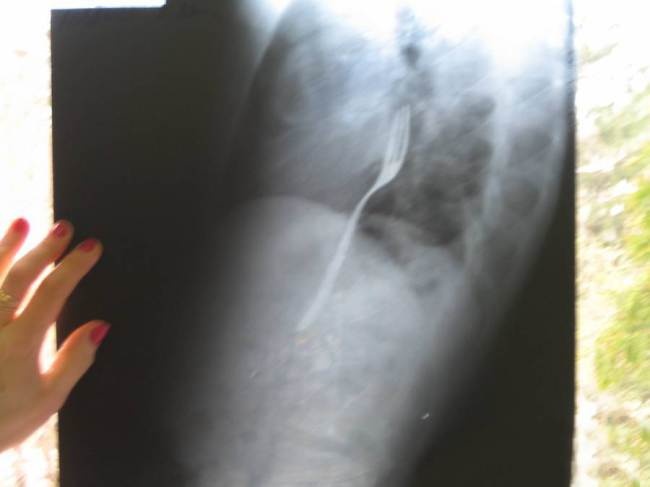

Một nam thanh niên người Romania nuốt dĩa và phải nhập viện trong tình trạng đau bụng dữ dội chỉ vì trò cá cược lúc say rượu.